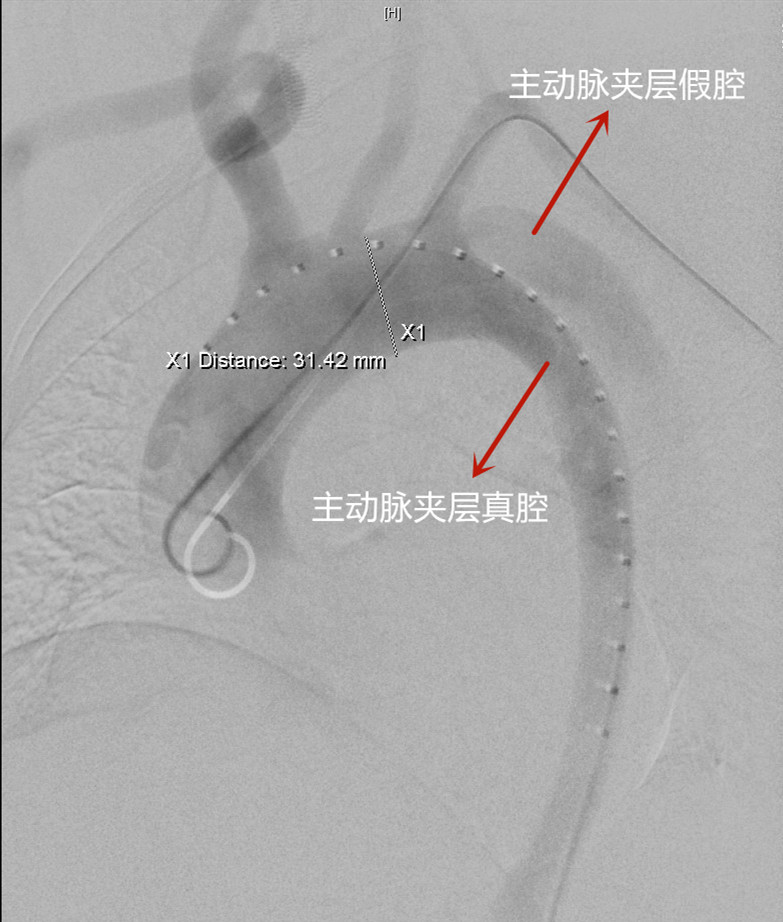

据血管外科主任吴巍巍介绍,人体主动脉壁有三层结构,内膜、中膜、外膜,当主动脉结构异常时,血流进入内、中膜之间,产生主动脉夹层,血液流入夹层假腔压迫真腔,导致突发、剧烈的胸背部撕裂样的疼痛,如不及时治疗,可导致夹层破裂大出血或缺血如脑梗死等,严重的可导致心衰、晕厥甚至突然死亡。

马士程立刻联系血管外科进行会诊。吴巍巍与副主任医师赵克强立即赶至急诊,然而严峻的问题摆在眼前:手术需要放支架,然而主动脉夹层已经很危重,影像还显示破口已经延伸左锁骨下动脉,如果放支架时堵住左锁骨下动脉,就会导致缺血,带来脑梗、肢体缺血甚至截瘫的风险;如果不封堵,就会因为支架无法彻底贴合夹层裂缝而导致内漏,仍有血液流入胸主动脉内、中膜之间,病根无法去除。

经反复研讨,吴巍巍团队最终为崔先生制定了“主动脉夹层腔内隔绝术+激光原位开窗技术重建左侧锁骨下动脉”方案:先用胸主动脉支架整体堵住夹层破口及左锁骨下动脉,再使用激光经左锁骨下动脉在主动脉支架上“开窗”打孔,植入支架,重建左锁骨下动脉血液通道。